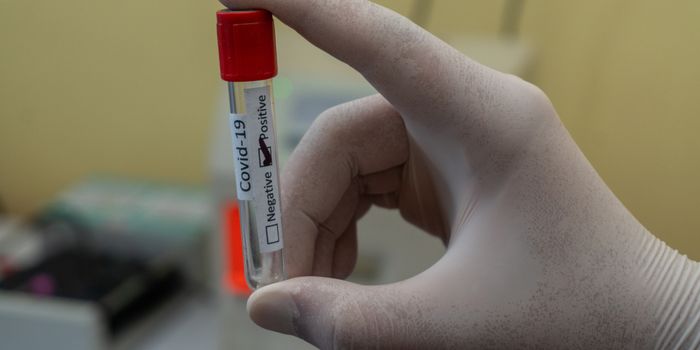

DEC 15, 2016Clinical & Molecular DXSilly Putty, the toy ubiquitous in nearly every household and elementary classroom, is the inspiration behind the latest ...